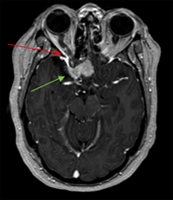

Benign brain tumor (memingioma, green arrows) compressing and affecting optic nerve (visual nerve, red arrow).

Mr. Fontanelli – Custom stereotactic radiotherapy

A 55-year old otherwise healthy accountant recently began experiencing headaches and right eye vision changes. Following a successful surgery for a meningioma (benign but locally destructive tumor) of the base of skull, scans confirmed residual tumor remaining along the optic nerve (responsible for vision).

For patients with partial resection of meningioma, post-operative radiation therapy is often required to prevent recurrence and the need for a difficult second surgery and associated risks. Achieving high dose to the tumor in the such close proximity to the nerve of the eye (optic nerve) with standard techniques can pose an undue risk for vision decline or complete vision loss.

An advanced radiation technique termed stereotactic radiotherapy was customized for Mr. Fontanelli. This allowed the curative treatment of his tumor, while minimizing radiation dose and side effect risks to the eye, optic nerve, and normal brain. He tolerated therapy well and continued work full time as an accountant during therapy.